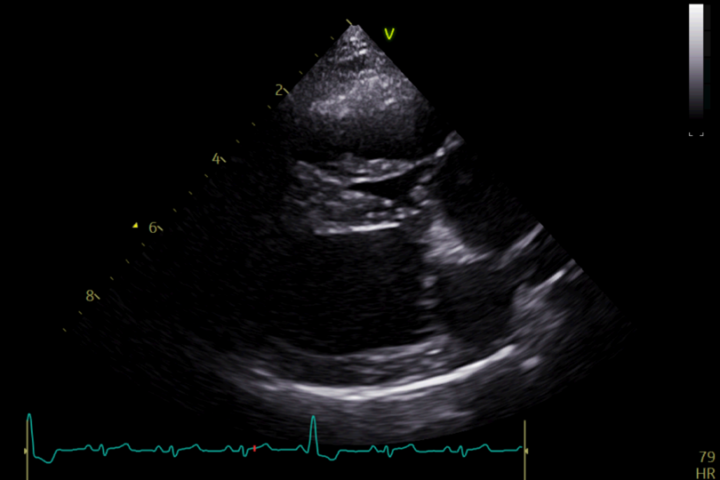

Surgical intervention is considered the treatment of choice for moderate to severe PS. Balloon valvuloplasty (BVP), a minimally invasive procedure, involves the insertion of a balloon catheter into the stenotic pulmonary valve and inflation to dilate the narrowed area (Figure 2). This technique has demonstrated excellent short- and long-term outcomes in dogs with valvular stenosis, with significant improvements in clinical signs and survival rates.

Complications of BVP include arrhythmias and haemorrhage. Moreover, some dogs might not fully respond to BVP with only a minor reduction in PS severity (reduction of 50 percent or more is considered successful).

In cases where BVP is unlikely to be successful (such as in cases with mixed-type PS), pulmonary artery stenting may be pursued. This is a minimally invasive technique that involves the implantation of a metal stent across the stenotic lesion (Borgeat et al., 2021). Complications for this procedure, besides those listed for BVP, include stent fracture, migration and crimping.